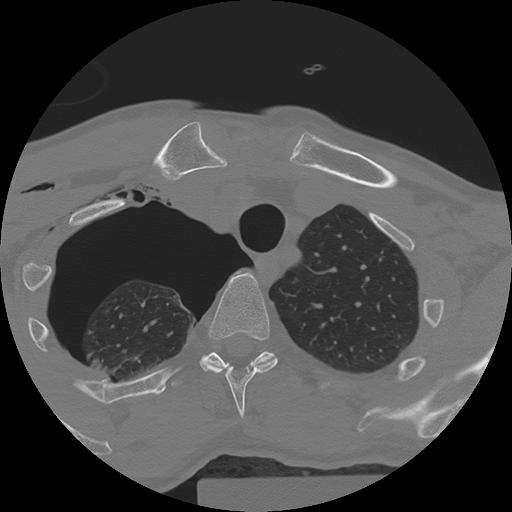

11 HUESO,,Axial,2.0,HUESO,,